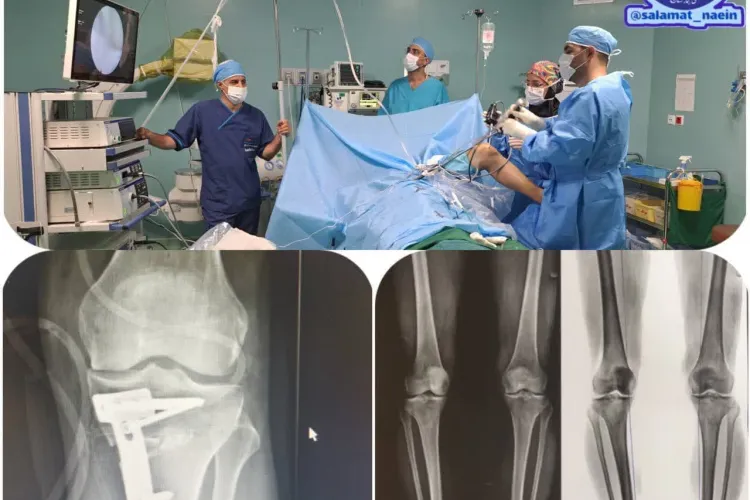

نخستین عمل جراحی همزمان اصلاح پای پرانتزی و ترمیم منیسک زانو به روش آرتروسکوپی در بیمارستان حشمتیه نایین

روز سهشنبه ۹ خرداد ماه انجام عمل جراحی تخصصی و پیچیده اصلاح پای پرانتزی و ترمیم منیسک زانو با آرتروسکوپ توسط دکتر حسنی متخصص ارتوپدی و تیم اتاق عمل بیمارستان حشمتیه نایین انجام شد.

لازم به ذکر است دستگاه آرتروسکوپی و وسایل جانبی آن با اعتباری بالغ بر ۵۰۰ ملیون تومان توسط خیرین بزرگوار سلامت شهرستان تهیه گردیده است.

آرتروسکوپی یک روش جراحی تقریبا بسته است که پزشک میتواند بوسیله آن مشکلات مختلف مفصلی را تشخیص و درمان کند.

طی این روش بر روی مفصل بیمار معمولا دو یا سه برش بسیار کوچک(کمتر از یک سانتیمتر) ایجاد شده و از طریق آنها دوربین بسیار ظریف آرتروسکوپ جهت اقدامات تشخیصی درمانی وارد مفصل بیمار می شود .

این روش به پزشک این امکان را میدهد که بدون نیاز به برش بزرگ و باز کردن مفصل، وضعیت مفصل بیمار را روی مانیتور مشاهده و اقدامات درمانی لازم را انجام دهد.

گفتنی است جهت درمان پارگی منیسک و رباط های صلیبی و بسیاری بیماریهای دیگر زانو، امروزه از آرتروسکوپ استفاده می شود.